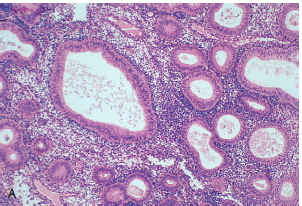

What does the endometrium look like during the proliferative phase of the menstrual cycle

The glands are round, proliferative, and contain mitotic figures (not curly)

What does the endometrium look like during the secretory phase of menstruation?

In the early phase, secretions inside the glands start to be seen and they become corkscrew shaped and sub-nuclei vacoules that eventually secrete into the lumen of the glands